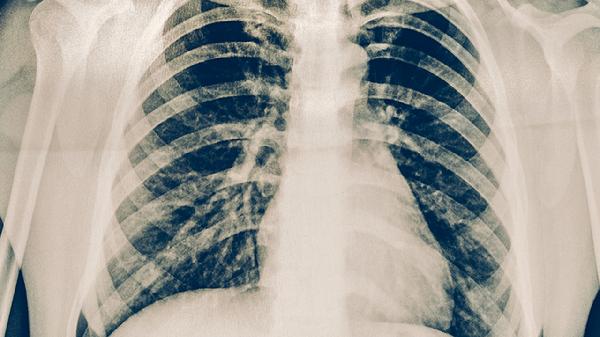

服药期间应每周监测体重变化,保持每日鸡蛋、瘦肉等优质蛋白摄入量100-150克,限制动物内脏、海鲜等高嘌呤食物。进行关节疼痛视觉模拟评分记录,疼痛持续加重或伴随晨僵超过1小时需及时复查胸片和结核菌培养。保持居室通风干燥,湿度控制在50%-60%,睡眠时垫高疼痛关节减轻肿胀。治疗全程避免擅自停用抗结核药物,需在结核科医生指导下完成规范疗程。